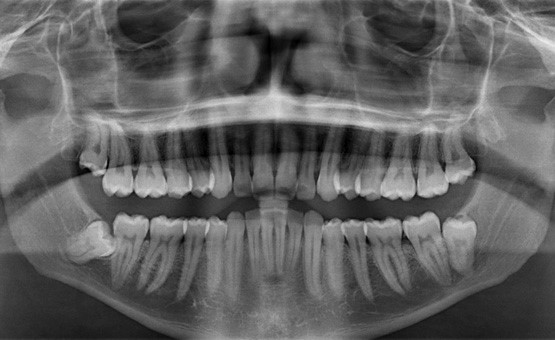

Дентальные снимки и диагностика кариеса